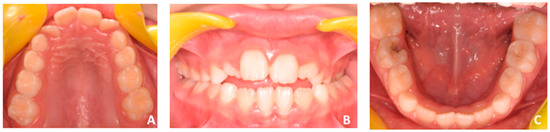

2.1. Patient’s Clinical Characteristics

2.4. Diagnosis and Treatment Plan

3. Results